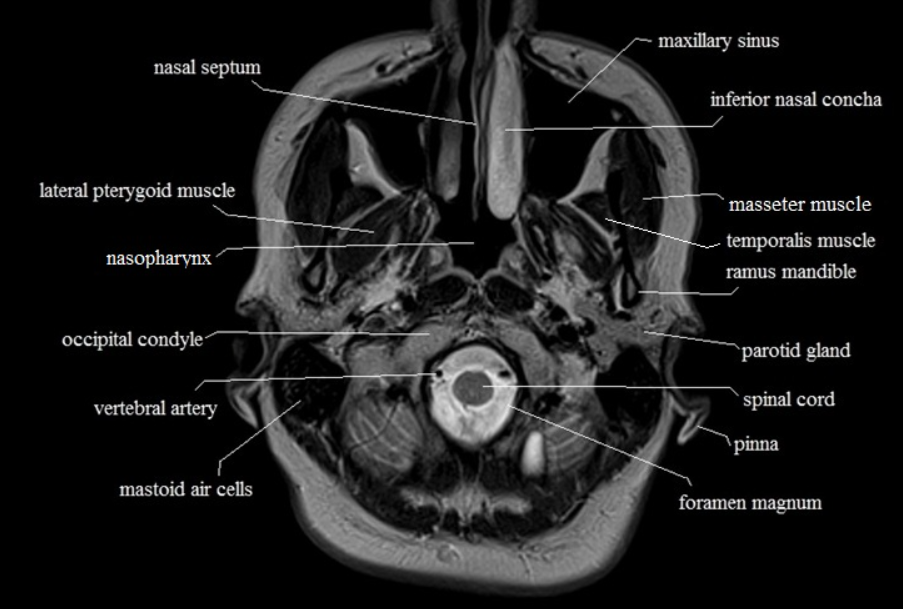

아래에서부터 올라간다. 중간에 있는 spinal cord 부분이 오늘 우리가 볼 해부학적 구조이다. 아래에서부터 내려가니 당연히 spinal cord부터 나온다.

올라가다 보면 뒤쪽으로 소뇌가 나오고 연수(medulla)가 나온다. 연수는 소뇌와 분리되어 있음을 알 수 있다. 아래에서부터 올라가다가 소뇌가 나온다면 소뇌의 아랫부분정도의 level에서 medulla가 나온다.